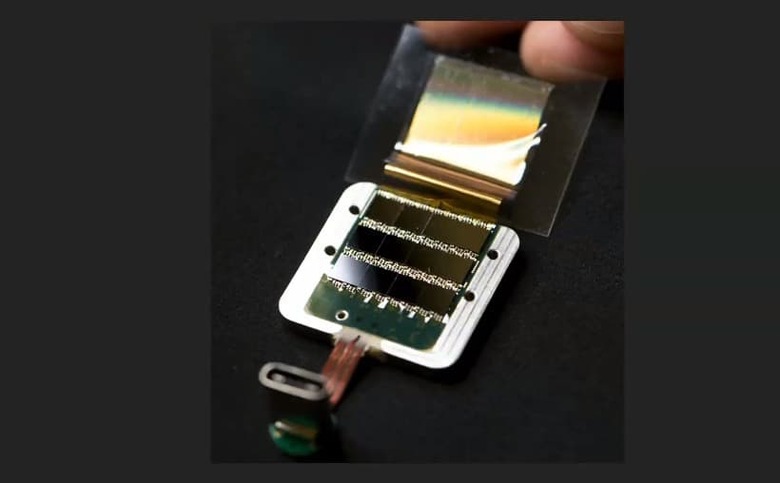

According to the article, its bundles of flexible threads are about one quarter the diameter of a human hair, implanted using needles to avoid blood vessels on the brain's surface. Then the embedded sensors capture information and send it to a receiver (the chip above) on the surface of the skull. From there it transmits wirelessly — Elon Musk said it could Bluetooth the information to your skull. Right now implantation requires drilling holes, but researchers hope in the future they can use lasers to avoid "unpleasant" vibration.

According to Musk, its current v1 4x4mm chip is capable of 10,000 electrodes with "read and write" capability, which he says is more than 1,000 times the number of the best deep brain interface currently available for Parkinson's treatment.